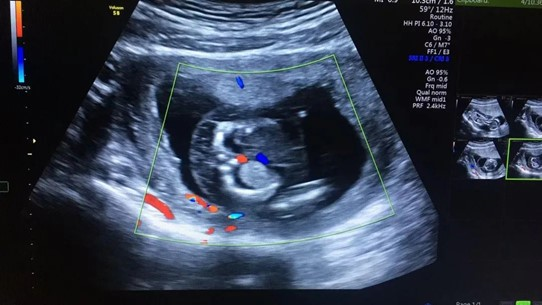

張女士本來(lái)是打算到武漢仁愛(ài)醫(yī)院做完產(chǎn)檢后,就和家人一起回老家過(guò)春節(jié),沒(méi)想到超聲檢查篩查出胎兒全身皮膚水腫,頸部淋巴水囊瘤,雙側(cè)胸腔積液,檢查醫(yī)生立刻叫來(lái)了武漢仁愛(ài)醫(yī)院超聲科主任王娟進(jìn)行再次檢查,確診了胎兒的異常情況。

張女士超聲檢查結(jié)果

“在這種情況下,胎兒需要進(jìn)行染色體的進(jìn)一步檢查,如果染色體有問(wèn)題,就要盡早終止妊娠?!蓖蹙杲榻B,造成這一現(xiàn)象最常見的原因是孩子的染色體異常,在得了淋巴水囊瘤的孩子中,有70%是存在染色體異常的,這個(gè)和年齡相關(guān),年齡越大發(fā)生的概率越高,而這些孩子在早期如果出現(xiàn)了水腫,90%以上都不能夠存活,所以建議盡早終止妊娠。